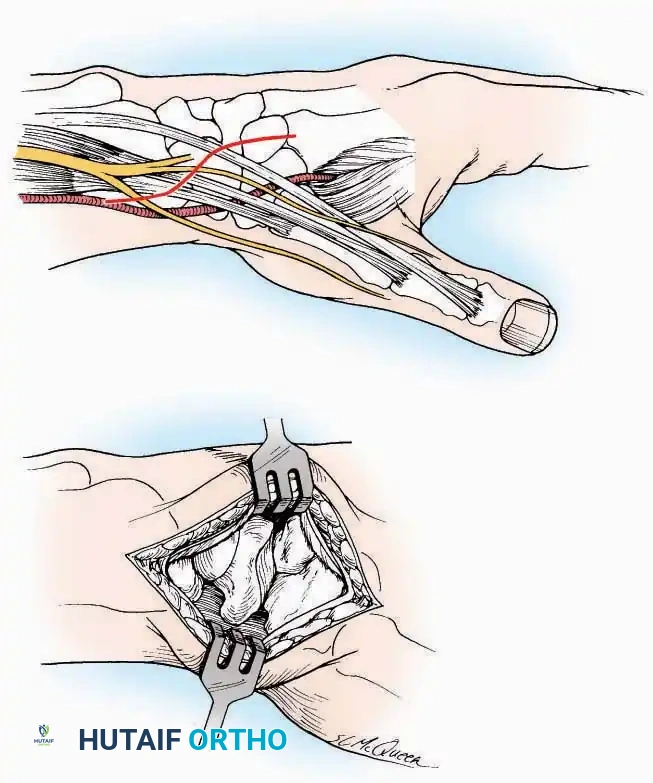

* Great Toe: Make a 2.5 cm longitudinal incision strictly on the medial midaxial aspect of the toe.

* Fifth Toe: Utilize a lateral midaxial incision to avoid interdigital maceration.

* Lesser Toes (2nd, 3rd, 4th): Approach the IP joints through a dorsal longitudinal incision placed just lateral to the corresponding extensor digitorum longus (EDL) tendon.

* Deep Dissection: Carry the dissection sharply through the subcutaneous tissue and superficial fascia directly to the joint capsule.

* Neurovascular Protection: Reflect the skin edges with meticulous care. Retract the dorsal digital nerves and vessels dorsally, and the plantar nerves and vessels plantarward.

* Capsulotomy: Open the capsule either transversely (for joint resection/arthrodesis) or longitudinally (for exploration), exposing the articular surfaces.